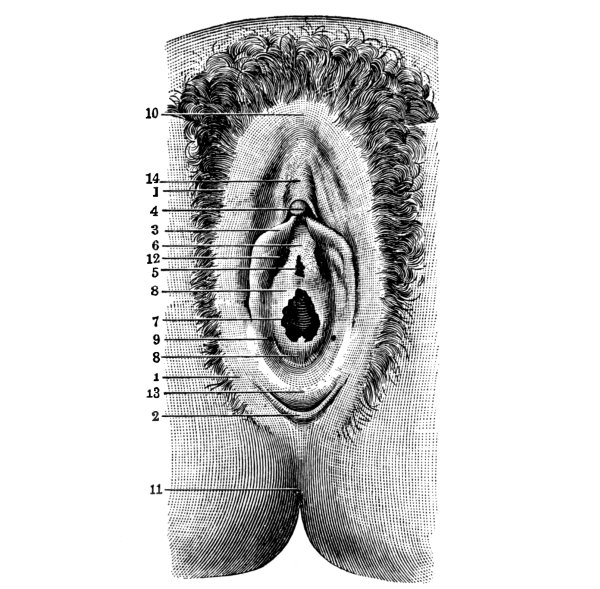

The Pelvis, 161—The Male Generative Organs, 164—The Prostate Gland, 164—The Testes, 165—The Penis, 165—The Female Generative Organs, 165—The Ovaries, 165—The Fallopian Tubes, 166—The Uterus, 167—The Vagina, 168—The External Genitalia in the Female, 169—The Vulva, 169—The Mons Veneris, 169—The Labia Majora, 169—The Labia Minora, 170—The Clitoris, 170—The Meatus Urinarius, 170—The Hymen, 170—The Fourchette, 170—The Perineal Body, 170—The Perineum, 170. |